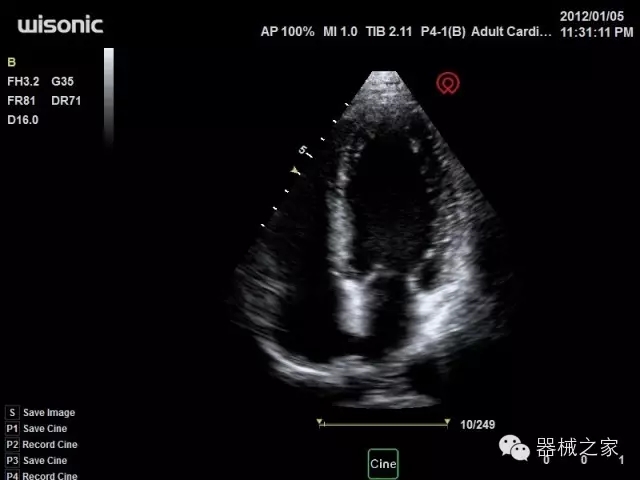

臨床圖片賞析

產(chǎn)品特點

·全球目前唯一一款配備主機雙探頭接口,整機重量(含電池)在5公斤以內(nèi)的便攜式彩超;

·獨有的HoloTM PW 實時3取樣門PW成像技術(shù),精確進(jìn)行血管診斷;

·一鍵優(yōu)化B、Color、PW,Auto Doppler自動識別血管位置、偏轉(zhuǎn)角度等,提高工作效率;